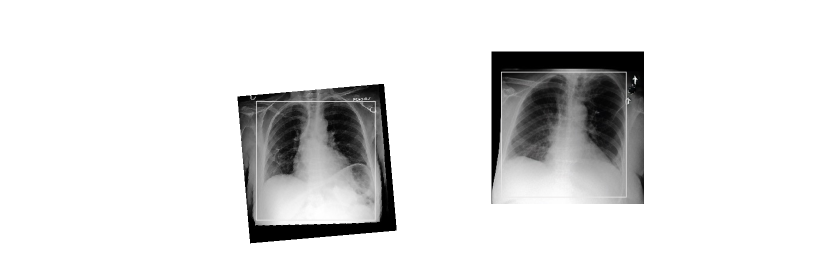

Refer to caption

Figure 3: The generated chest X-ray images of the MIMIC-CXR dataset with highlighted regions.

Fig. 3 presents a comparison of CXR images generated by our method and existing approaches on both the MIMIC-CXR and OpenI datasets. In the first example, our proposed method successfully synthesizes the ’opacity near the aorta’ described in the input report, while other methods struggle to generate this specific feature. This observation highlights the superior capability of our method in producing highly realistic and accurate CXR images that faithfully reflect the content of the corresponding reports.